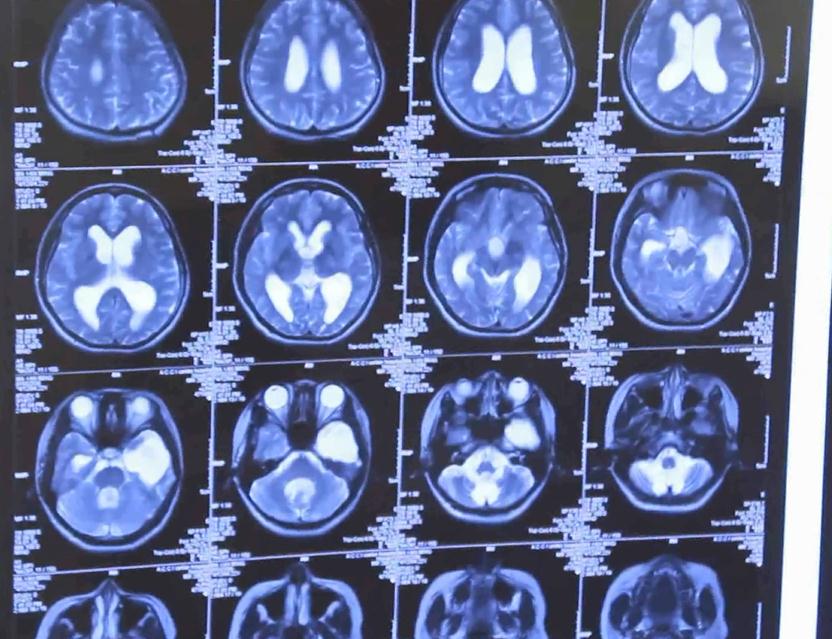

根据问诊情况和检查评估,确认小虹大脑颞叶部位放电异常,并且已经十五年的病史。“做脑电图发现她双侧放电都挺多的,而且一发作就是大发作,很严重。”,认为小虹情况符合手术指征。与病人家属沟通后,张教授为小虹实施了左侧颞叶标准切除术。手术历时七个小时,非常成功。

手术后检查一切正常

手术到现在一年多了,小虹恢复得特别好。再次给小红复查后介绍,癫痫也不发作了,大脑核磁复查也没什么问题,小姑娘精神状态也不错,效果还是比较理想的。小虹的父亲说:“之后没有发作过,现在挺好的,能自己自由行动,大人也不用跟着照看。”